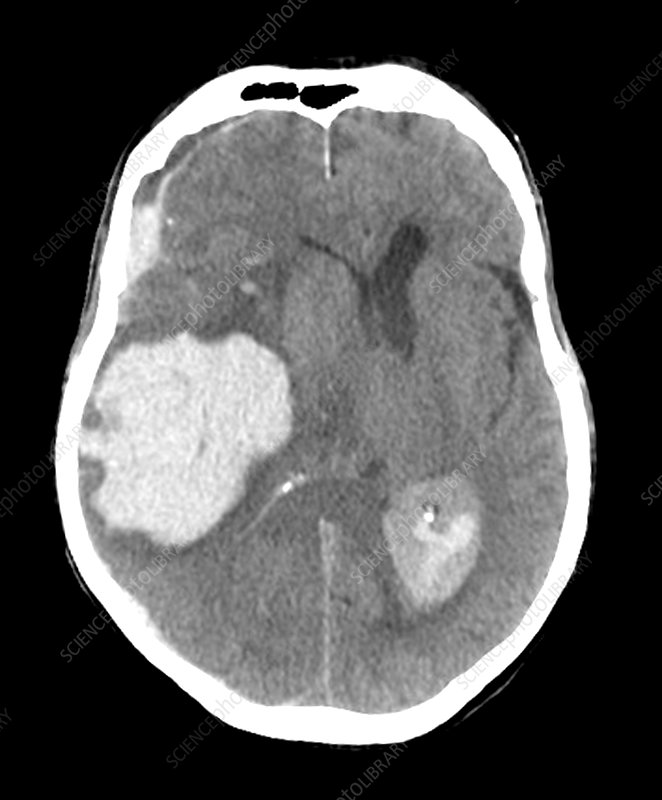

- Midline shift: Displacement of midline structures (falx cerebri, septum pellucidum) suggests mass effect from haemorrhage, tumour or major oedema.

- Haemorrhage: Hyperdense areas. Classify as epidural, subdural, intraparenchymal, or subarachnoid based on location and shape.

| Intracerebral / intraparenchymal haemorrhage | Hyperdense collection within brain parenchyma with variable mass effect. Appearance depends on location and size; may extend into ventricles. |

| Haemorrhagic stroke | Hyperdense intraparenchymal blood clot with or without surrounding oedema and mass effect; may have intraventricular extension. |